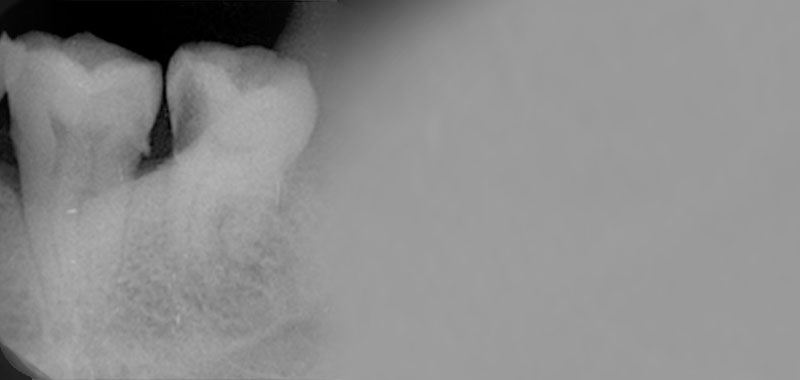

左邊下面的水平阻生智齒蛀牙(黑色的部分就是被蛀牙掏空的齒質)